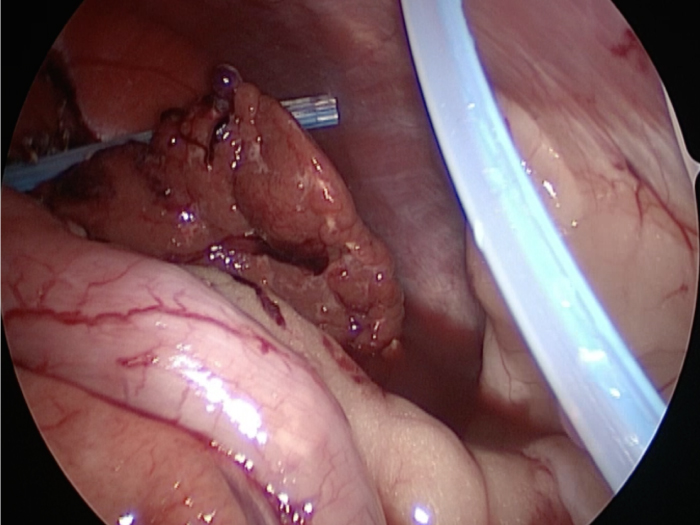

胆嚢が破裂した様子を腹腔内にカメラを入れて観察した像です。

胆嚢から漏れ出た胆汁が腹腔内に確認できます

摘出した胆嚢はカチカチで中にはゼリー状の硬い物質が詰まっていました。

胆嚢は分厚くなり周りには脂肪が張り付いていました。